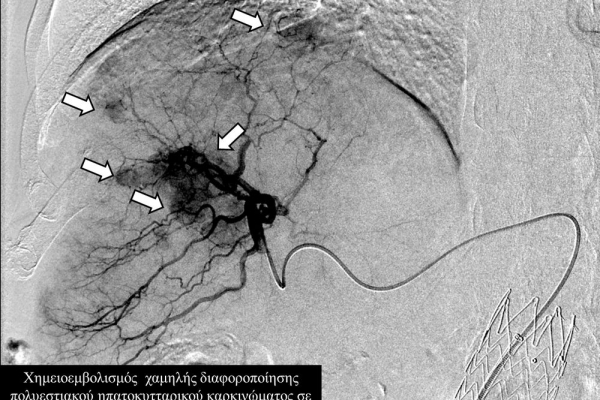

Ο χημειοεμβολισμός έχει καθιερωθεί σαν θεραπεία εκλογής στο ενδιάμεσο στάδιο του ηπατοκυτταρικού καρκινώματος.